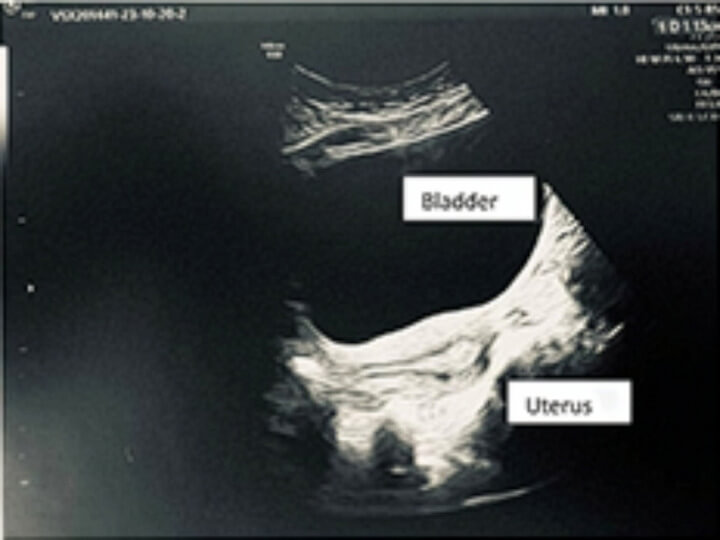

Die Auflösung kommt in der Untersuchung unter Narkose: Die Harnröhrenöffnung ist massiv erweitert – so weit, dass ein Finger ohne Widerstand hindurchpasst, während Urin unwillkürlich austritt. Direkt darunter befindet sich eine winzige Vaginalöffnung. Der Verdacht bestätigt sich: Geschlechtsverkehr fand über Jahre hinweg nicht vaginal, sondern über die Harnröhre statt.

Die Diagnose erklärt die gesamte Symptomtrias: Dyspareunie durch Fehlpenetration, Belastungsinkontinenz und wiederkehrende Harnwegsinfekte. Die Behandlung umfasste eine Vaginaldilatation, eine Empfehlung zur Urethroplastik und gezieltes Beckenbodentraining. Zudem erfolgt eine weitere Abklärung im Rahmen der Infertilitätssprechstunde.